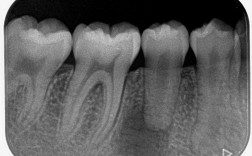

牙齿矫正是改善牙齿排列和咬合关系的有效方法,而拔除智齿往往是矫正过程中的关键步骤,智齿生长位置不正、空间不足或影响其他牙齿排列时,拔除智齿能为矫正提供更好的条件,本文将详细介绍拔除智齿与牙齿矫正的关系,并结合最新数据帮助读者做出科学决策,为...